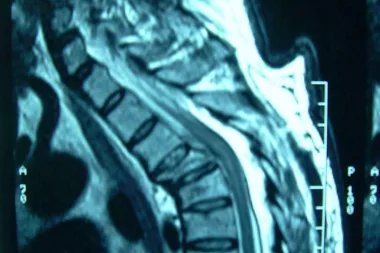

Las fracturas vertebrales, por Neurocirugía Galarza